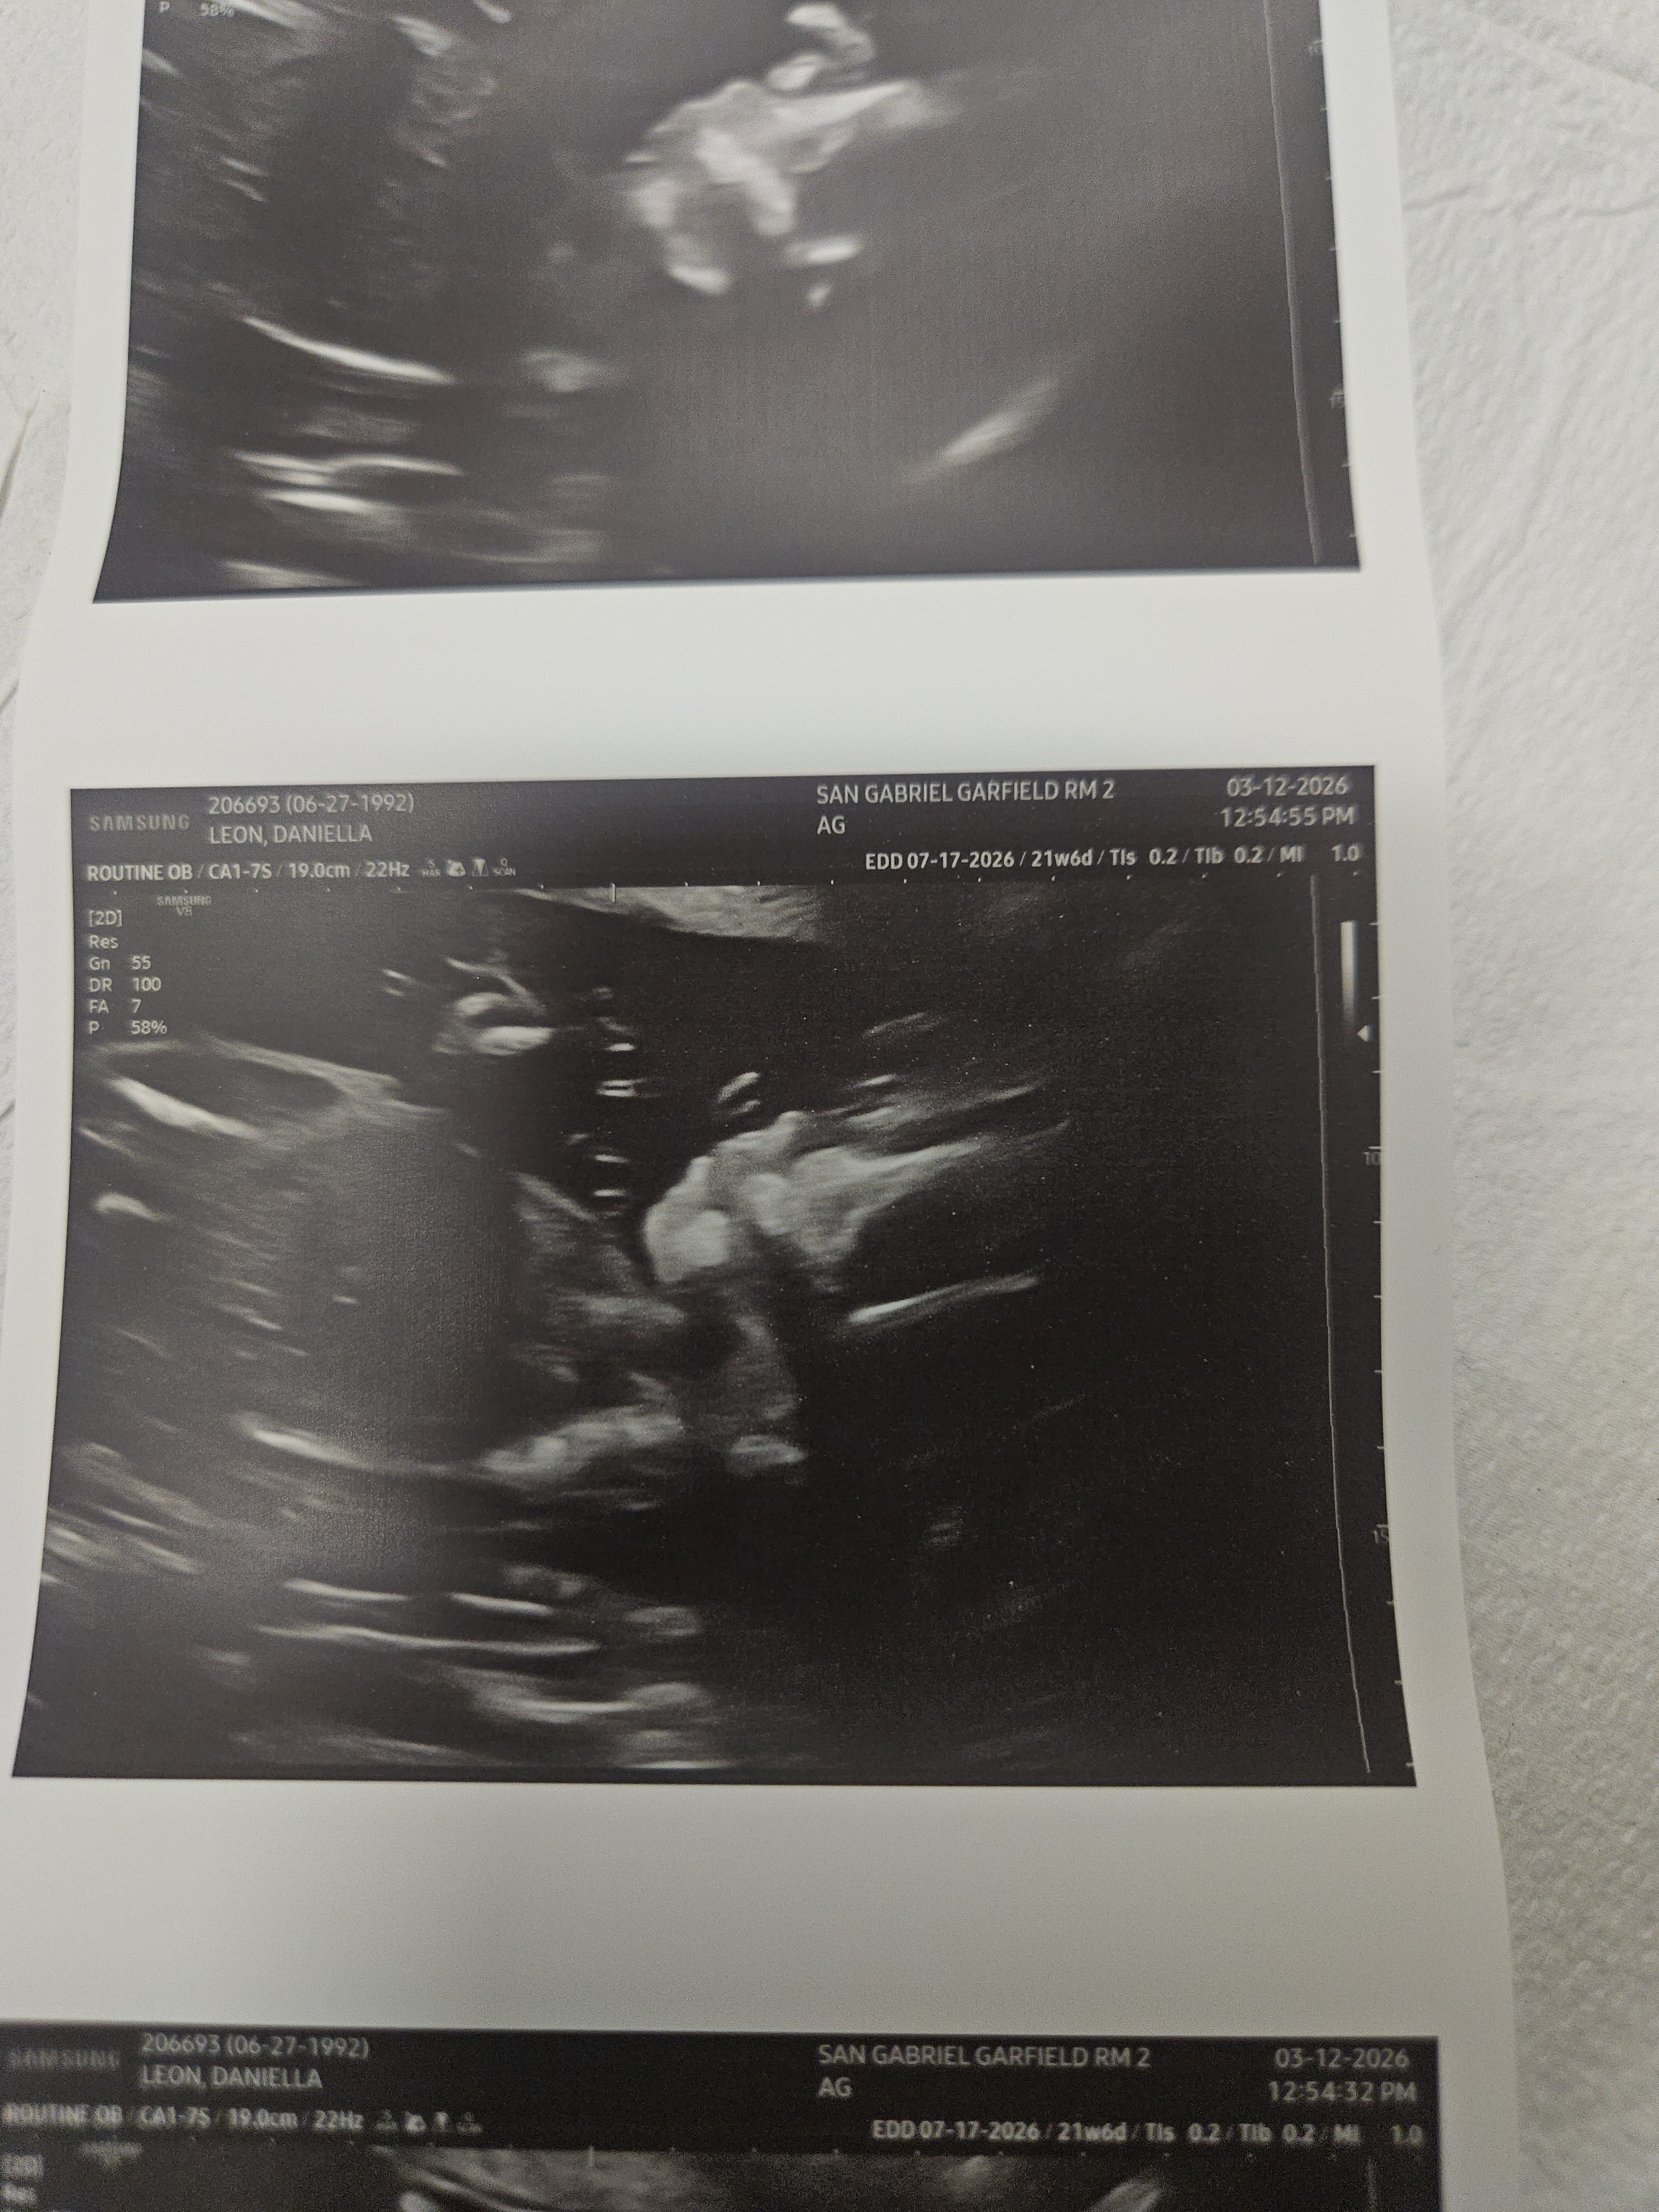

Hello, everyone. My name is Lala. My husband's name is Brian. Unfortunately, I had to come here and ask for help from family members, friends, and anybody who maybe has gone through this and knows how tough it can be. But just at twenty-two weeks and four days, on Monday night, my water broke and I went into labor. I delivered my baby boy, Brian Jr., on March 17th. Tragically, he was only able to spend eleven minutes with us before passing away in his father's arms. The overwhelming loss of our baby boy has brought unimaginable pain and grief, and Brian and I are left to lean on one another as we try to navigate this overwhelming loss.